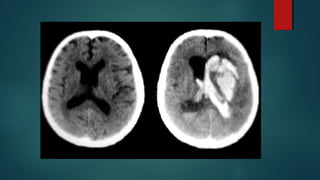

Este documento es el programa para un taller de imágenes del curso de emergencia 2015 impartido por el Dr. Víctor Delgado. El taller se centra en el uso de imágenes médicas para el diagnóstico y tratamiento de pacientes en coma traumático según la base de datos de Marshall. El Dr. Delgado es el único instructor repetido a lo largo del documento.